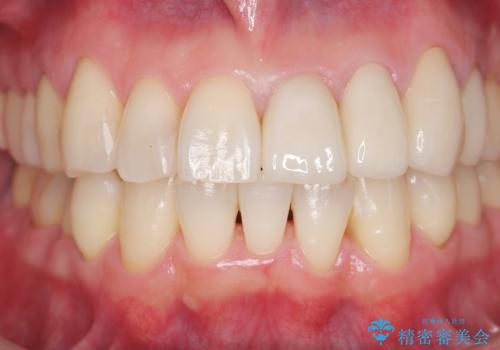

セラミック治療を行うことで、虫歯の再発リスクをおさえ、審美的な前歯の見た目を回復することができました。